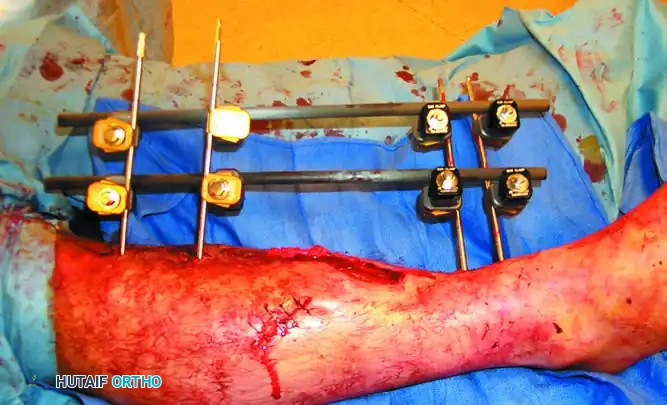

2. Pin Insertion Technique

- Incision: Make a longitudinal stab incision (1-2 cm) through the skin. Do not use a puncture technique, as skin tension around the pin leads to necrosis and infection.

- Blunt Dissection: Use a hemostat to bluntly dissect down to the periosteum. Insert a tissue protection sleeve (drill guide) firmly against the bone.

- Pre-drilling: Always pre-drill the near and far cortices using a sharp drill bit. Use continuous saline irrigation to cool the drill bit. Thermal necrosis from drilling is the primary cause of premature pin loosening and ring sequestrum formation.

- Pin Placement: Insert the half-pin manually or on low speed. Ensure the pin engages the far cortex but does not protrude more than 1-2 threads to avoid tethering far-side soft tissues.

3. Frame Assembly and Reduction

- Apply the pin-to-bar clamps to the pins.

- Attach the longitudinal carbon fiber or titanium rods.

- Perform the fracture reduction under fluoroscopic guidance using manual traction.

- Once length, alignment, and rotation are restored, sequentially tighten all clamps.

- Verify the final reduction and ensure the frame is 2-3 cm away from the skin to accommodate swelling.